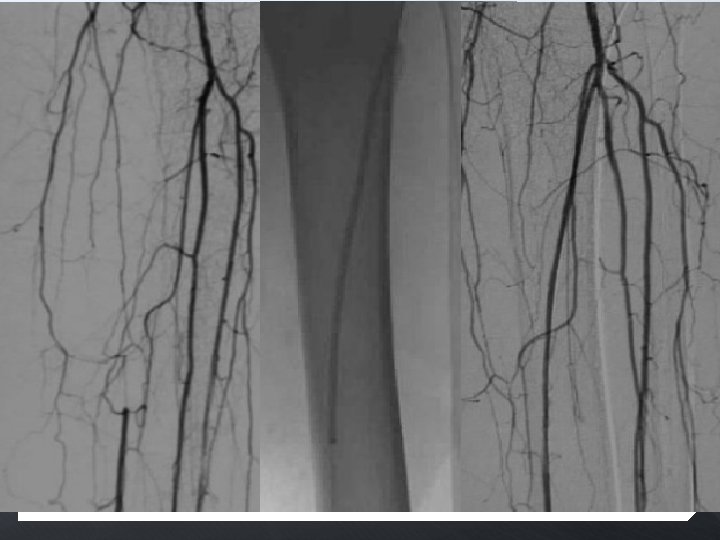

SFA